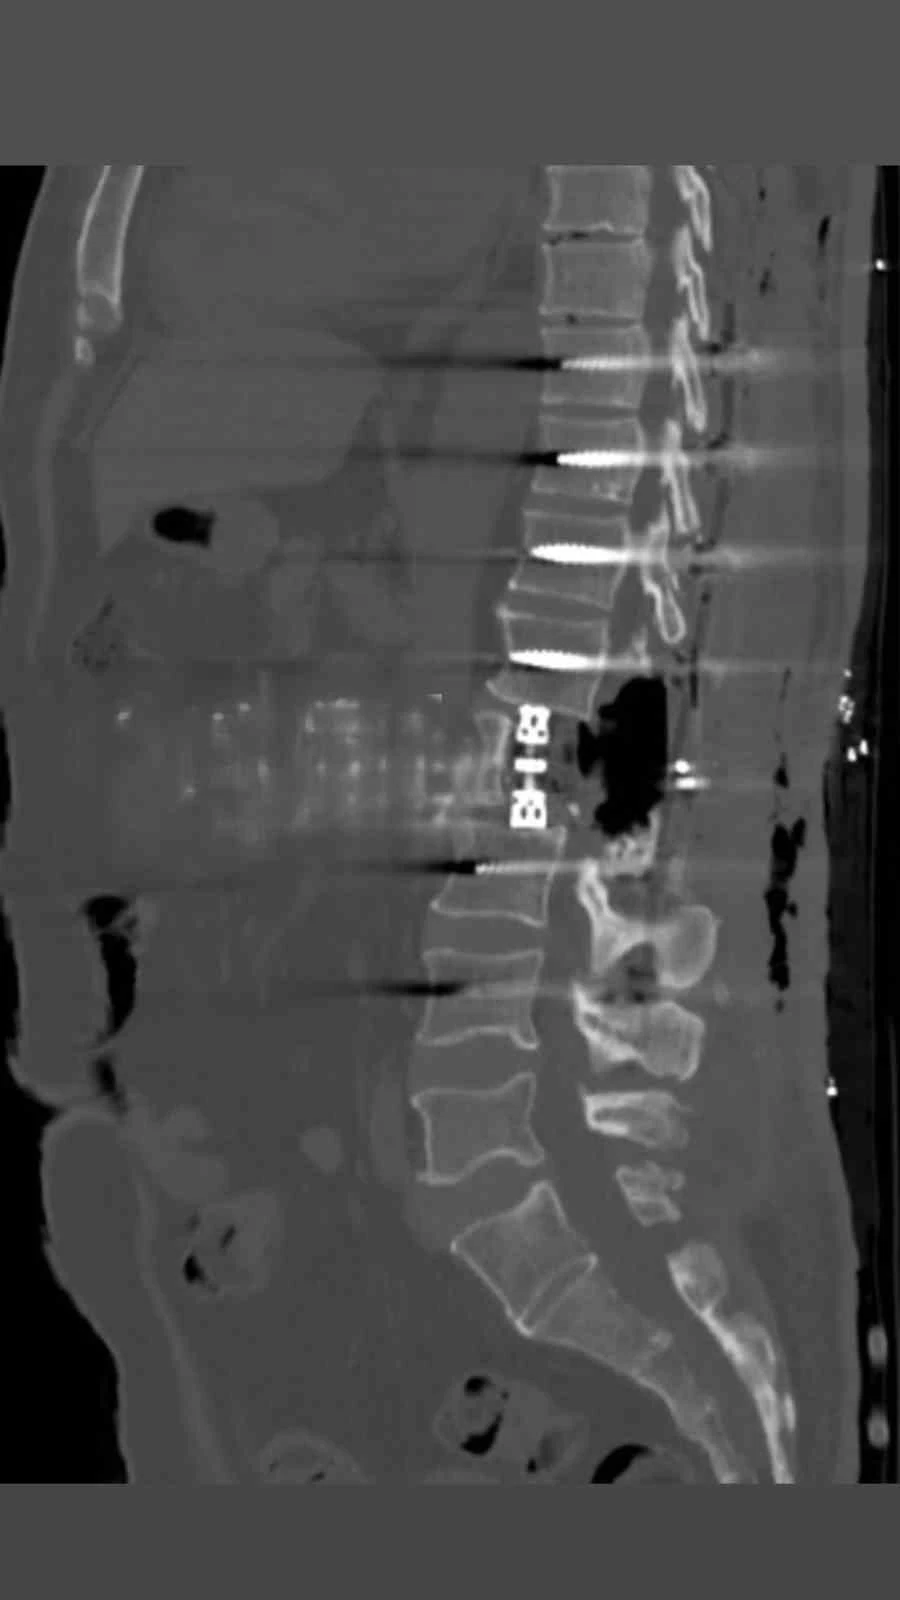

Bayburt Devlet Hastanesinde omurga bölgesindeki tümörler yapılan korpektomi işlemiyle alındı. Omurganın bir kısmının cerrahi olarak çıkarılması işlemi olan korpektomi ameliyatı Op.Dr Aziz Kaan Erçandırlı ve Op.Dr Ali Emre Özer tarafından başarılı bir şekilde yapıldı.

Bayburt Devlet Hastanesine belli başlı şikayetlerle başvuran hastaya korpektomi ameliyatı yapılarak, hastanın tümörleri temizlendi. Hastanın bel omurundaki enfeksiyon temizlendikten sonra kafes ve enstrüman sistemi ile sabitleme yapıldı. Beyin ve Sinir Cerrahisi Uzmanları Op.Dr Aziz Kaan Erçandırlı ve Op.Dr Ali Emre Özer tarafından yapılan operasyonla, hasta sağlığına kavuştu.